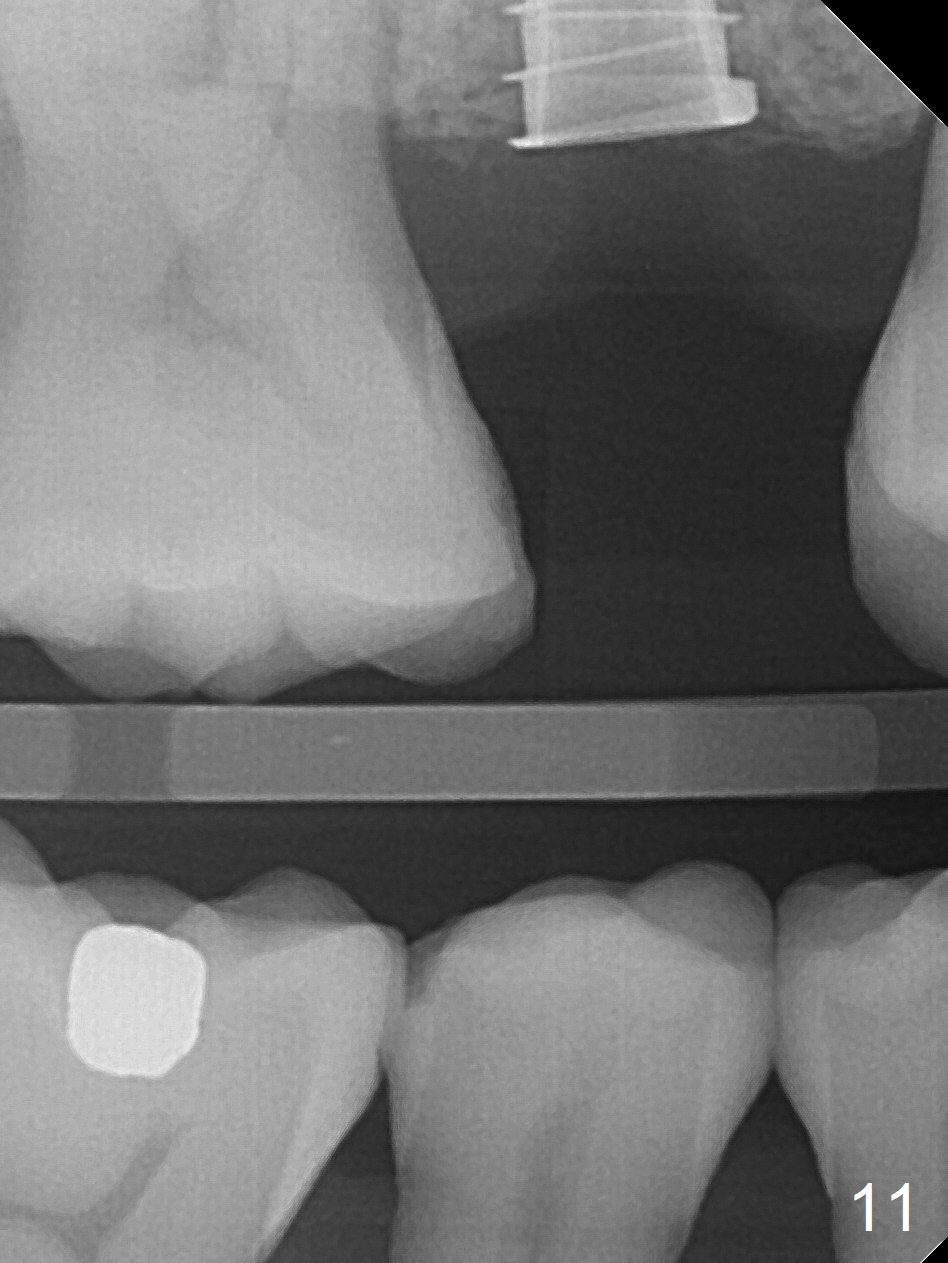

A 47-year-old man returns emergently with subgingival fracture of the lingual (L) cusp of the tooth #4 (Fig.1-3).  After extraction (no bony defect) without drilling, a 4x11 mm dummy implant is placed as a tap drill with satisfactory stability (Fig.4,5).  To get subcrestal placement, a shorter (4x9 mm) implant is inserted with insertion torque of < 35 Ncm.  In retrospect, a larger implant (4.5 mm) would be better in term of primary stability.  After allograft placement into the buccal and lingual gaps, a 4.5x4(4) mm abutment is placed for an immediate provisional.  There is a peri-implant gap 7 months postop (Fig.7<, as compared to the implant at #2 (6 months postop)) .  When the loose abutment is being retightened, the patient feels pain, although the gingiva appears healthy (Fig.8).  A larger implant should have been used; the abutment should have been removed.  The implant dislodges while the abutment is untightened 8 months postop.  The osteotomy is found intact.  A 4.5x11 mm dummy implant is placed 2 mm subgingival with 20 Ncm (Fig.9).  When a 4.5x11 mm definitive implant is placed 3 mm subgingival (Fig.10,11), torque reaches 50 Ncm.  A 5.5x3 mm healing abutment is placed.  Three months postop, the implant is stable (Fig.12,13) and impression is taken.